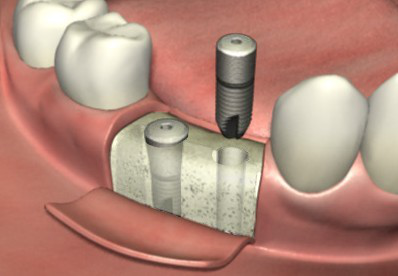

1、手术前要先做个口腔全景片,以确保牙槽骨适合做种植牙,之后再由医生设计出具体的种植方案。>>>推荐阅读:廊坊圣洁口腔数字化导航种植

2、手术开始,先在牙槽骨上备孔并植入种植体(人工牙根),然后等待3~6个月的骨结合期。